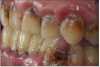

Patient presents with maxillary and mandibular anterior teeth having been extracted and is wearing transitional removable appliances.

Decisions need to be made as to smoking cessation, periodontal treatment and tooth replacement. The photos and dental radiographs were taken prior to the referral (Figure 23 through Figure 25), and the periodontal charting done post-op (Figure 26).

Figure 23.

Figure 23